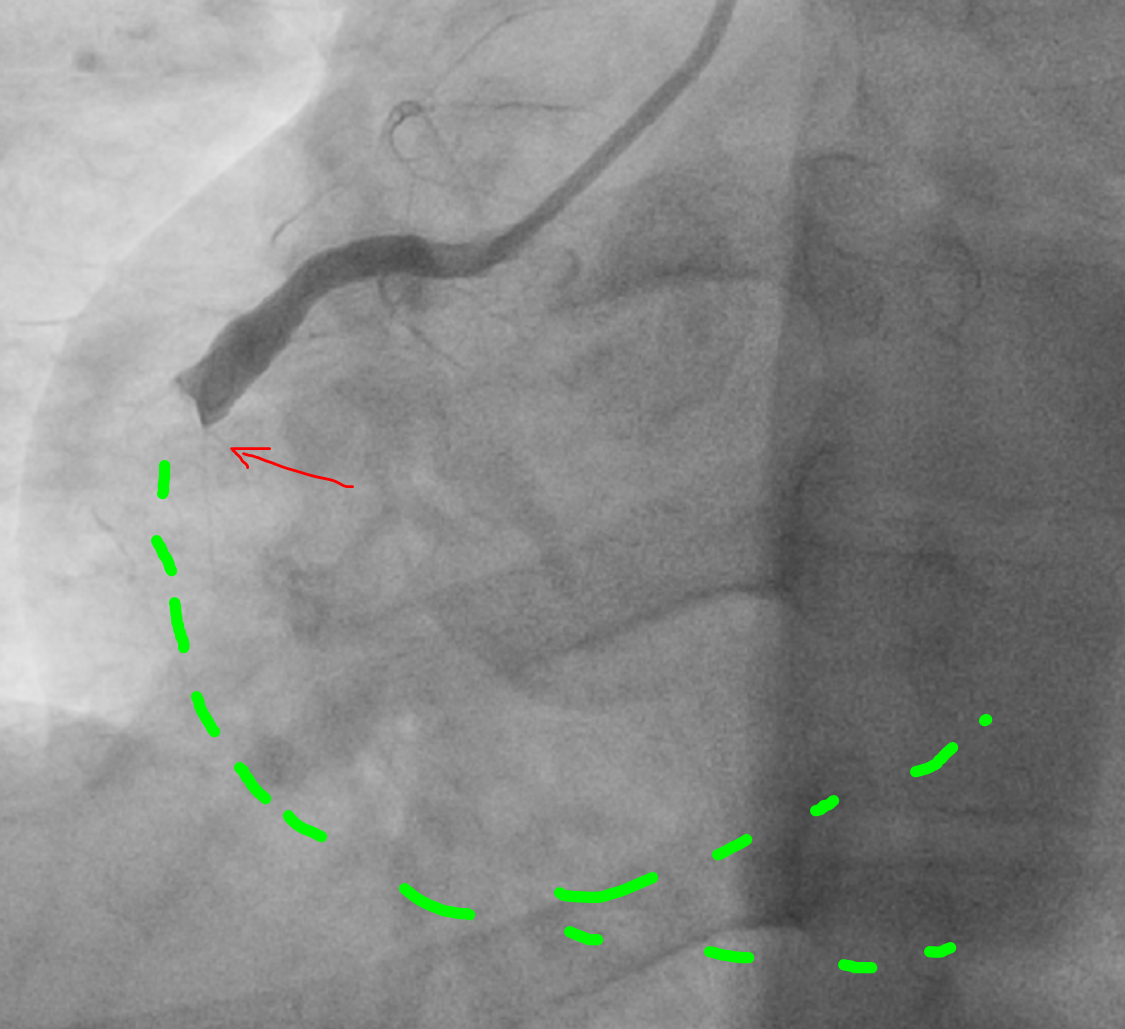

И что мы видим?

Далее реканализация окклюзии и удаление тромбов